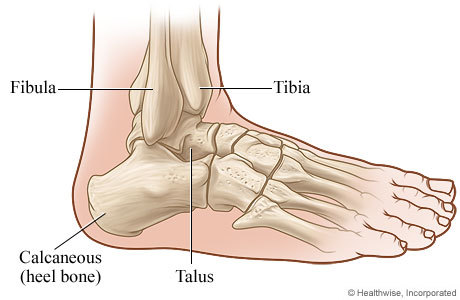

The ankle joint (talocrural joint) is a hinge-type synovial joint located in the lower limb, formed by the bones of the leg and the foot – the tibia, fibula and talus

The subtalar joint is a planar synovial joint formed from the articulation between two of the talus and calcaneus bones of the foot